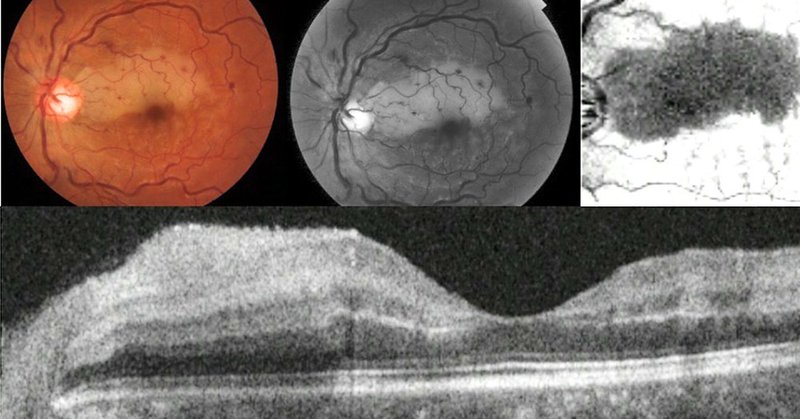

👁️New study from @Moorfields calls for full investigation of systemic disease links for patients with PAMM lesions in largest multi-ethnic cohort to date. 🔎In @AJOphthalmology Led by @LimoliCeleste @LaxmiDRaja & @pearsekeane @h_a_khalid @JosefHuemer1

Patients with the eye condition Paracentral Acute Middle Maculopathy (PAMM) would benefit from further investigation, as their risk of heart attacks and strokes may be greater than previously shown,...